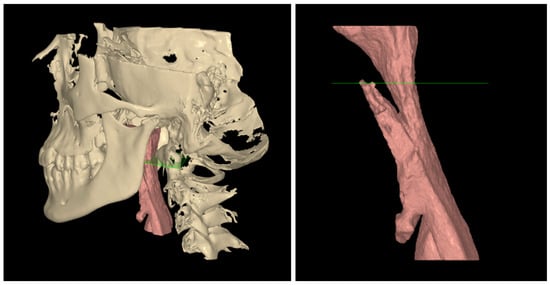

2.2. Condyle Volume Calculation